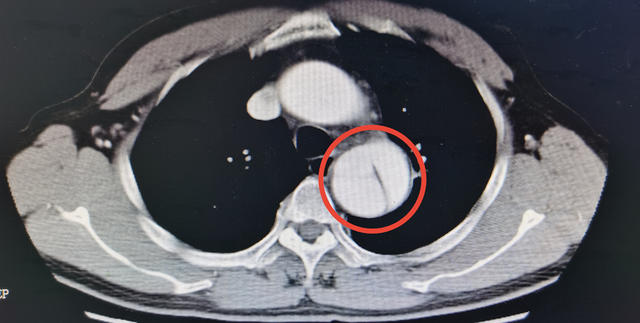

男子咳嗽4个月不见好转检查却发现致命的主动脉夹层